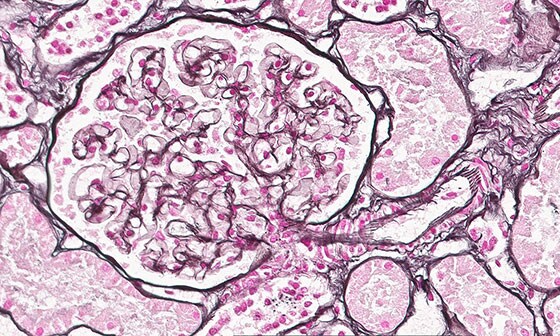

Pathologists study disease - by examining cells and tissue sample – and work together in a multidisciplinary team of doctors, scientists, nurses and healthcare professionals to diagnose, treat and prevent illness [1]. Their work underpins every aspect of patient care, from diagnostic testing and treatment advice to the use of cutting-edge genetic technologies. Pathology was until recently one of the last bastions of medicine not to have been digitized.

The authorization by the FDA for digital pathology in the US, the world’s largest healthcare market, constitutes a watershed moment for the healthcare industry. Pathologists work in laboratories, in clinics and on hospital wards. Digital pathology enables them to view and diagnose digital images of surgical pathology slides prepared from biopsied and resectioned tissue. It means we can leverage all the benefits that result when images are digitized, including the reporting and billing of diagnostic results.

Rather than looking directly at a tissue sample mounted on a glass slide under a conventional light microscope, the Philips IntelliSite Pathology Solution enables pathologists to read and share tissue slides digitally in order to make diagnoses. It could help make critical health information available to patients and healthcare professionals faster and at lower cost.

The ultimate aim of digitization is that all sorts of algorithms – such as image analysis to aid the pathologist in making better and faster decisions – will be developed and become clinically available. Ultimately, this will create even more opportunities for digital innovation – using artificial intelligence for computational pathology and other innovative technologies – that could support increased accuracies, predictive health management or ultimately potentially improve patient outcomes. [1] The Royal College of Pathologists